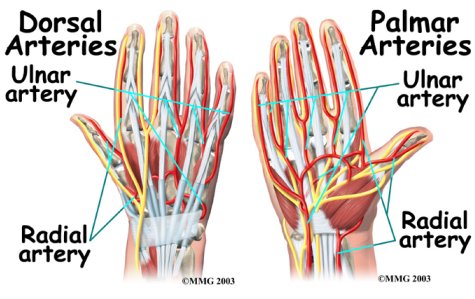

Traveling along with the nerves are the large vessels that supply the hand with blood. The largest artery is the that travels across the front of the wrist, closest to the thumb. The radial artery is where the pulse is taken in the wrist. The ulnar artery runs next to the ulnar nerve through Guyon's canal (mentioned earlier). The ulnar and radial arteries arch together within the palm of the hand, supplying the front of the hand, fingers, and thumb. Other arteries travel across the back of the wrist to supply the back of the hand, fingers, and thumb.